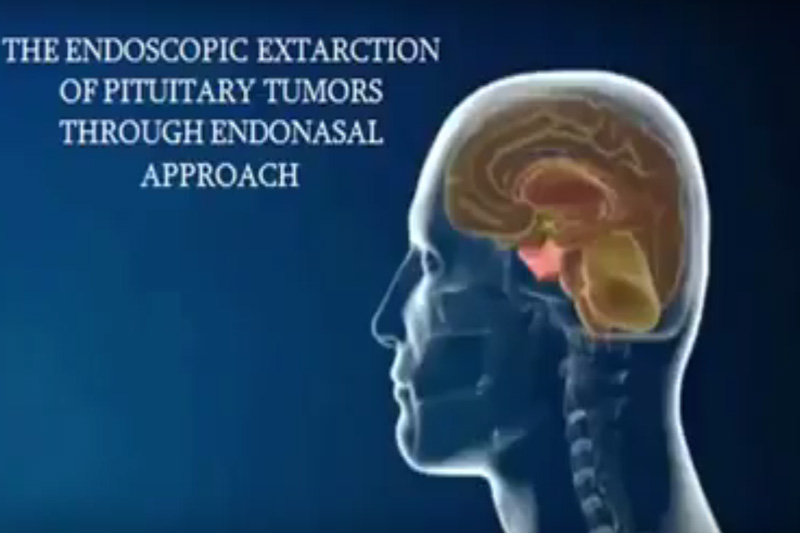

Служба осуществляет диагностику и лечение острых и хронических нарушений мозгового кровообращения, различных центральных и периферических заболеваний нервной системы воспалительного, аутоиммунного, посттравматического генеза, двигательных нарушений, а также минимально инвазивные оперативные вмешательства при различных патологиях головного и спинного мозга.